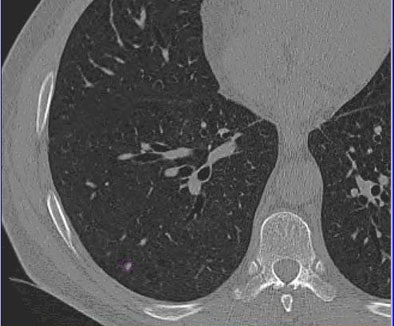

![]() |

| Images of solid lung nodules include uncompressed CT data (above), 24:1 compression (below), 48:1 compression (next down), and 96:1 compression (bottom). CAD detection performance of solid lung nodules greater than 4 mm in size did not suffer until 48:1 compression, and was found to be robust up to 96:1 even when the subjective visual appearance of the compressed images was degraded. The results suggest that 3D lossy wavelet compression can be performed without significant loss of CAD detection performance, which can minimize data storage and ultimately facilitate the implementation of CAD technology in a PACS environment. Images courtesy of Philippe Raffy, Ph.D. |